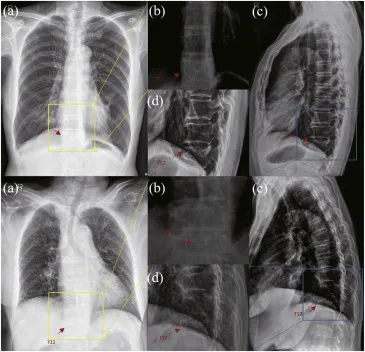

图1. 准确识别椎体压缩性骨折的主要挑战。图1展示了两种异常骨折(轻度/重度)病变区域及其在不同模态中相邻正常椎体的比较。(a)、(b)分别是胸部正位X光片及其放大视图;©、(d)分别是胸部侧位X光片及其放大视图。箭头指示T12椎体的病变区域。